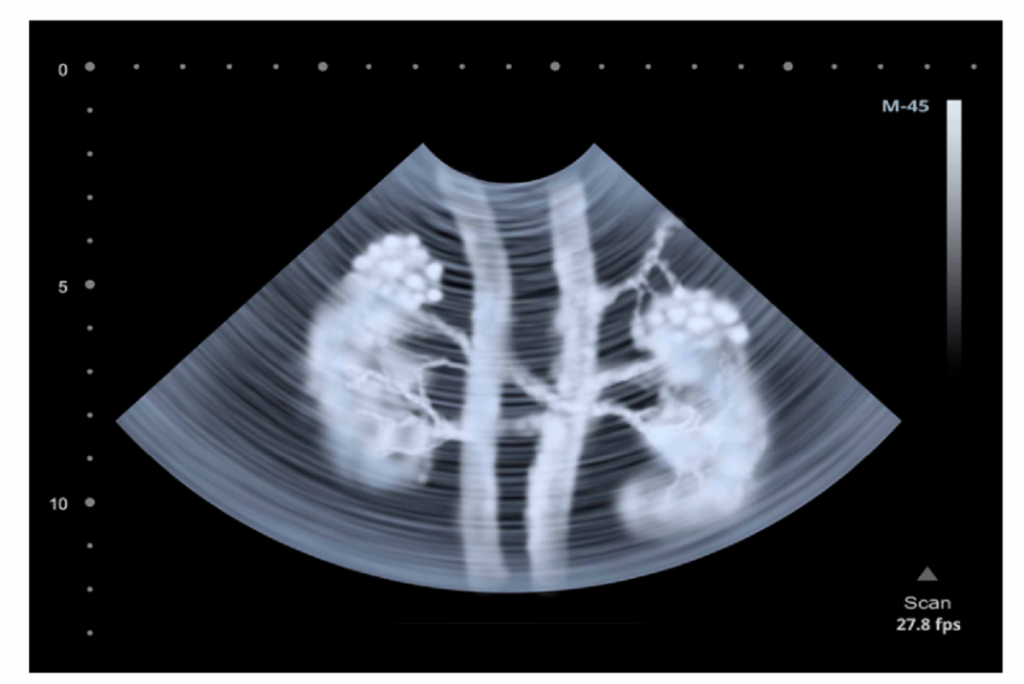

بیماری کلیه پلی کیستیک (Polycystic Kidney Disease) یک اختلال ارثی مربوط به بافت کلیه است. در این بیماری کیست های پر از مایعات در کلیه شکل میگیرد. بیماری کلیه پلیکیستیک ممکن است عملکرد کلیه را مختل کرده و در نهایت باعث نارسایی آن شود.

برای تشخیص هر سه نوع بیماری کلیه پلی کیستیک ، پزشک شما ممکن است از آزمایشات تصویربرداری برای جستجوی کیست کلیه، کبد و اندام های دیگر استفاده کند. آزمایشات تصویربرداری مورد استفاده برای تشخیص PKD شامل موارد زیر است: